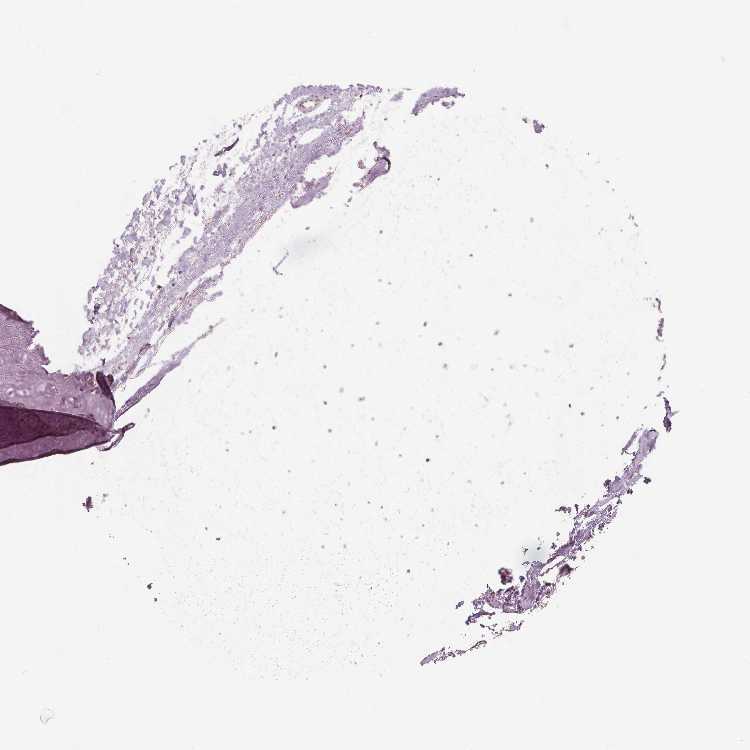

SOFT TISSUE 1 - Antibody stainingi

Antibody staining in the annotated cell types in the current human tissue is reported as not detected, low, medium, or high, based on conventional immunohistochemistry profiling in selected tissues. This score is based on the combination of the staining intensity and fraction of stained cells.

Each image is clickable and will lead to virtual microscopy that enables deeper exploration of all samples and also displays staining intensity scores, fraction scores and subcellular localization as well as patient and tissue information for each sample.

Antibody HPA025070Antibody HPA025293Antibody HPA027233

Chondrocytes Not detectedNot detectedMedium

Fibroblasts Not detectedNot detectedNot detected

Peripheral nerve Not detected--